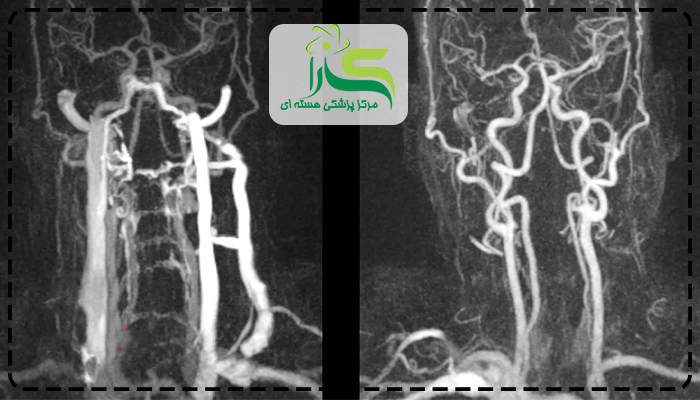

مراحل انجام آنژیوگرافی به این صورت است که یک لوله نازک را از ساعد یا کشاله ران وارد رگها کرده و از این لوله یک مایع رنگی به داخل رگها می فرستد که این کار سبب می شود رگ ها در تصویر به خوبی مشاهده شوند و نواحی مسدود شده قابل تشخیص باشد. پس از انجام آنژیو این رنگ از طریق ادرار از بدن خارج خواهد شد.

از آنجایی که آنژیوگرافی نیز نوعی اسکن می باشد که از طریق آن بسیاری از رگهای باریک، مسدود و یا بزرگ شده مشاهده می شوند. در برخی افراد این روش جنبه درمانی نیز دارد. در صورت مشاهده ی هر گونه گرفتگی عروق با لخته خون پزشک در صورت نیاز به درمان و باز کردن عروق می پردازد.

تفاوتهای اسکن هستهای قلب و آنژیوگرافی شامل نوع روش، میزان تهاجم، دقت و کاربردهای آنها است. اسکن هستهای قلب بیخطر است و بیشتر برای بررسی عملکرد عضله قلب استفاده میشود، در حالی که آنژیوگرافی تهاجمی است و برای مشاهده مستقیم رگها و شناسایی انسدادها کاربرد دارد.

در مقایسه دقت و کاربرد نشان میدهد که اسکن هستهای قلب برای تشخیص اختلال جریان خون مفید است، اما آنژیوگرافی اطلاعات دقیقتری درباره محل انسداد و شدت آن ارائه میدهد. پزشکان ابتدا اسکن هستهای قلب را انجام میدهند و در صورت نیاز به بررسی مستقیم رگها، آنژیوگرافی را تجویز میکنند.

مزایا و محدودیتها اسکن هستهای قلب شامل خطر احتمالی و درد کمتر است، اما دقت آن در تشخیص انسداد شدید کمی کمتر از آنژیوگرافی است. آنژیوگرافی دقت بالایی دارد ولی به دلیل تهاجمی بودن ممکن است خطرات احتمالی خفیف مانند خونریزی، عفونت یا حساسیت به ماده حاجب ایجاد شود.